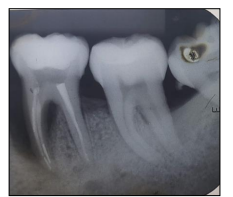

Observe a imagem a seguir:

Considere que o dente 46 possui uma coroa clínica com 9 mm de largura no sentido vestibulolingual; a sondagem horizontal da furca (vestibulolingual) foi de 6 mm; e, ainda, que havia uma parede óssea no lado lingual. É possível afirmar que, de acordo com a classificação de Hamp (1975), esse é um defeito de furca grau: